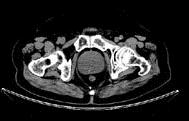

问题 男,65岁,尿频尿急及排尿困难,CT检查如图所示,下列说法错误的是 ( )

选项 A、此为前列腺增生 B、此为前列腺癌 C、其包膜光滑,境界清晰 D、与膀胱分界清楚 E、前列腺形态呈类圆形

答案 B